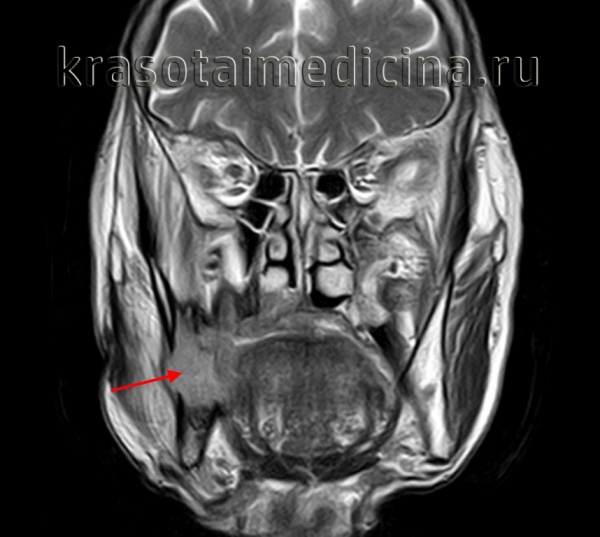

(Слева) На аксиальной МР-томограмме (STIR) визуализируется крупная амелобластома нижней челюсти, в составе которой находится массивный кистозный компонент (с правой стороны) с наличием уровней «жидкость-жидкость». Обратите внимание на многокамерный компонент с гиперинтенсивным сигналом на Т2ВИ (с левой стороны).

(Справа) При МРТ Т1ВИ FS сКУ в аксиальной проекции у это го же пациента с амелобластомой нижней челюсти определяется выраженное контрастное усиление стенок крупной однокамерной кисты, расположенной справа. Видны также множественные кисты меньшего размера с левой стороны.

(Слева) При MPT Т2ВИ с КУ в аксиальной проекции у пациента с амелобластомой верхней челюсти определяется солидный и кистозный (многокамерный) компонент. Обратите внимание на типичный интенсивный (Т2ВИ) сигнал в кистозном компоненте, а также экспансивное воздействие опухоли на заднюю стенку верхнечелюстной пазухи.

(Справа) На корональной (T1ВИ) томограмме с контрастным усилением и жироподавлением у этого же пациента определяется характерное контрастное усиление перегородок. Местно агрессивный характер амелобластомы также подтверждается ее распроаранением в полость носа и ячейки пазухи решетчатой кости.